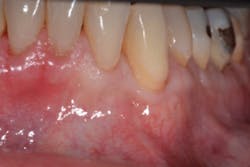

At least 2 mm of gingiva must be left on each side of the flap to preserve blood supply and avoid loss of crestal marginal bone. Although this technique is most effective in treating Miller Class I and II recession defects (figures 1 and 1a), it can be used to obtain partial root coverage around Miller Class III defects. This technique is best used around canines, premolars, and molars.

The Bernotti V-Y Flap involves making a submarginal supraperiosteal V-shaped incision 1 mm to 2 mm apical to the mucogingival junction, creating a pedicle flap (figures 2 and 2a). This flap is extended one tooth mesially and distally to the recession defect. It is important to note that the flap should leave the adjacent papillae intact in order to preserve blood supply. An intrasulcular incision is then made with a microsurgical blade to allow for coronal movement of the marginal tissue without tension (figure 3). The root is then scaled/root planed and chemically modified with an amoxicillin slurry for three minutes (figure 3a).